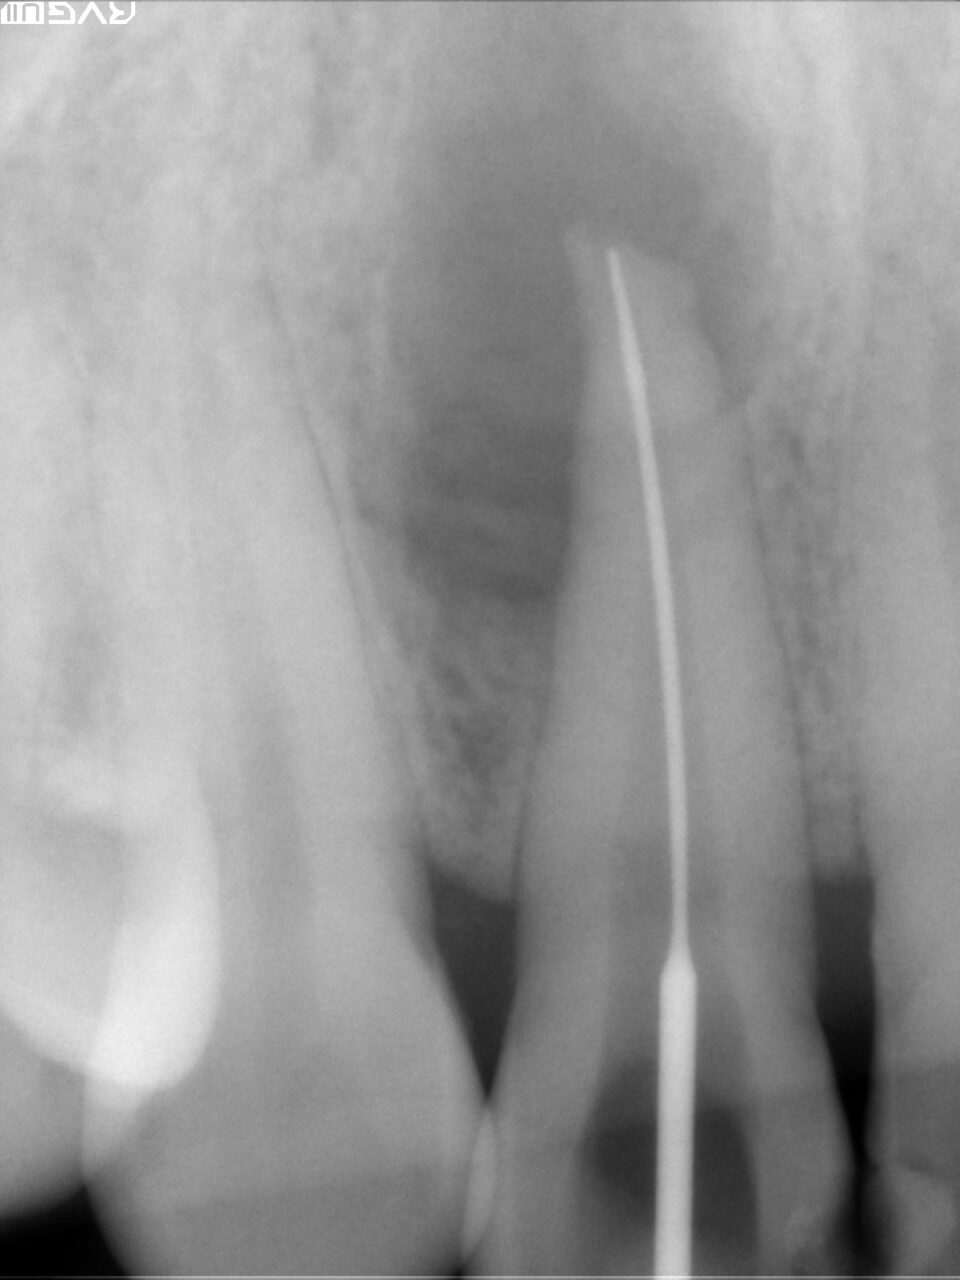

根尖までの長さや根尖孔の太さを確認するためにファイルを入れてレントゲン撮影を行います。

根管形成が終わり、根管洗浄を十分に行い、バイオセラミックによる根管充填を行ないました。

根尖部よりバイオセラミックが出ているが、臨床的には何も問題はありません。この語、骨が再生されるまでには数ヶ月時間かかります。